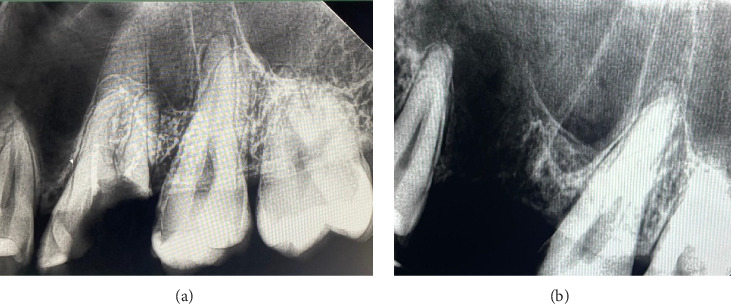

Background: Oroantral communications (OACs) are pathological openings between the oral cavity and the maxillary sinus, often resulting from dental extractions. If not treated promptly, they may lead to sinus infections and persistent oroantral fistulas (OAFs). Objective: This report aims to present a minimally invasive technique for the closure of OACs using flowable composite resin stabilized within a network of crossing sutures and to assess its clinical efficacy. Case Descriptions: Two male patients, aged 27 and 31, presented with OACs measuring 8 mm and 6 mm in diameter following maxillary molar extractions. Both cases were managed within 24-48 h postextraction. Intervention: Under local anesthesia, the extraction sockets were sutured using absorbable threads, creating a cross-matrix over the alveolus. Flowable composite resin was then applied into and over this suture network to form a sealing layer. The material was light-cured, and a secondary application was performed following socket curettage to promote stable blood clot formation. In this technique, the flowable composite is mechanically stabilized within the network of crossing sutures, which enhances the retention of the material, ensures effective sealing of the OAC, and supports a more predictable and secured healing process. Outcomes: In both cases, healing was uneventful, with complete closure of the OAC and no signs of sinusitis or fistula formation. Follow-up at 8 and 9 months confirmed successful mucosal healing and radiographic bone regeneration. Conclusion: The fixation of flowable composite within a suture matrix offers a novel, cost-effective, and reproducible technique for the immediate closure of small-to-moderate OACs. This approach enhances mechanical stability, improves sealing, and facilitates predictable healing while avoiding more invasive surgical interventions.